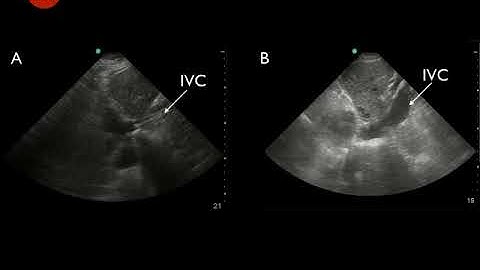

What is Collapsing and Non Collapsing IVC #echo #shorts